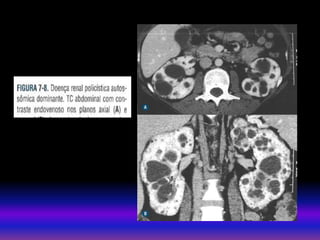

• TAC Sem contraste(litiases). uso contraste Depende da função renal . Util em doenças parenquimatosas ou vasculares. Há risco de NIC Pacientes com DRC estágio 3 – 4 se recomenda: Protocolos com baixa dose de contraste não ionico 60 – 100 ml. Útil hidratação endovenosa antes e após a exposição ao meio de contraste : SSN 250 ml/h x 4 horas (antes e depois) MÉTODOS DE IMAGEM